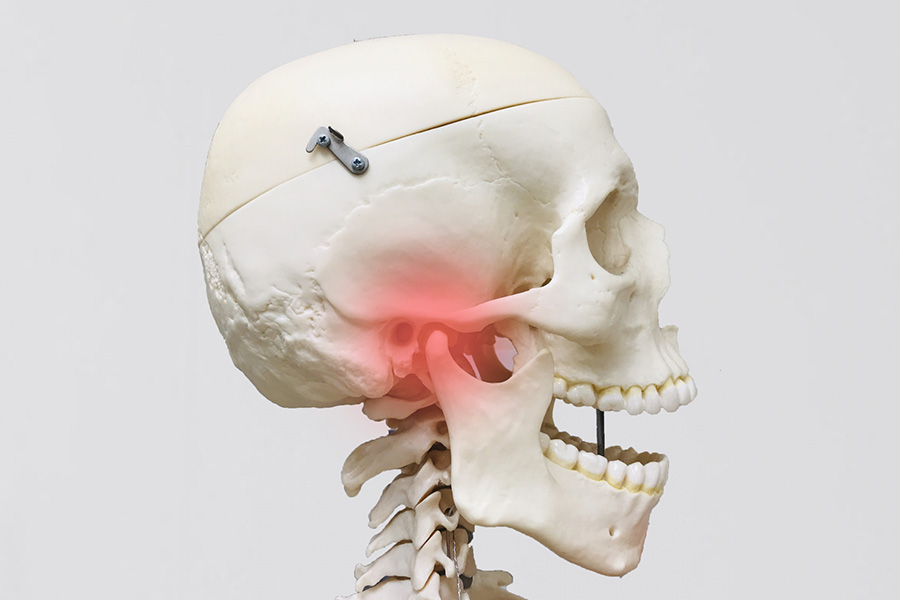

顎関節症

あごの痛みや関節音、口の開きづらさなどがある場合、顎関節症が疑われます。日常のクセやストレス、外傷などが関係しているとされており、重症化すると外科的な処置が必要になることもあります。早期の対応が大切です。